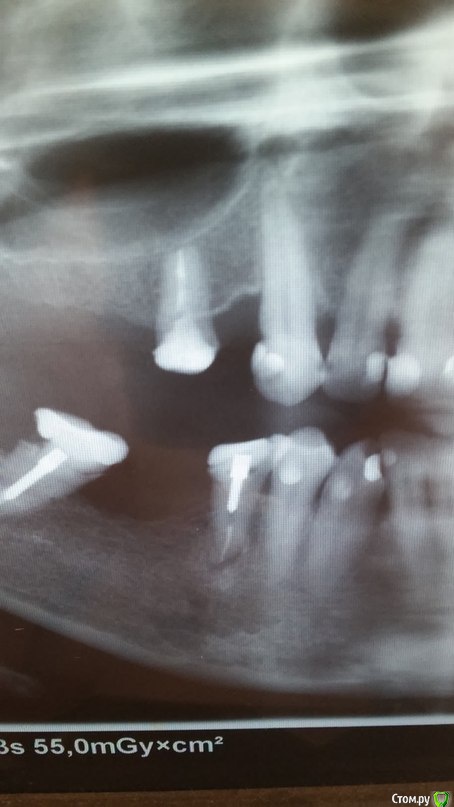

ksanta Опубликовано 31 мая, 2015 Поделиться Опубликовано 31 мая, 2015 (изменено) Здравствуйте! При накусывании и надавливании болит нижняя 5. Зуб на штифте (делали лет 10 назад). В чем может быть причина? Изменено 31 мая, 2015 пользователем ksanta Ссылка на комментарий

Паращук Роман Опубликовано 31 мая, 2015 Поделиться Опубликовано 31 мая, 2015 Проблема в воспалительном процессе. Возможно пропущен канал. Зуб разобрать,штифт удалить,оценить на наличие трещин,переделать канал-лы. 2 Ссылка на комментарий

Гарриевич Опубликовано 31 мая, 2015 Поделиться Опубликовано 31 мая, 2015 Воспалительный процесс на 5ке с уже начавшейся резорбцией корняКак писали коллеги выше, зуб перелечить и адекватно восстановить Ссылка на комментарий

ksanta Опубликовано 1 июня, 2015 Автор Поделиться Опубликовано 1 июня, 2015 не возможно, а необходимоно вопрос Вам нужно решать в целом с этим участкомСегодня врач посмотрел снимок и сказал, что только удалять. Лечить нет смысла. Ссылка на комментарий

ksanta Опубликовано 1 июня, 2015 Автор Поделиться Опубликовано 1 июня, 2015 на чем основан его вывод вы спросили?Сказал, что воспаление на корне. Показал хирургам, те тоже сказали удалять. Ссылка на комментарий

Гарриевич Опубликовано 1 июня, 2015 Поделиться Опубликовано 1 июня, 2015 (изменено) Сказал, что воспаление на корне. Показал хирургам, те тоже сказали удалять.Ответ неквалифицированного специалистаВоспаление на кроне не может быть обьективной причиной для удаления. Изменено 1 июня, 2015 пользователем Гарриевич Ссылка на комментарий